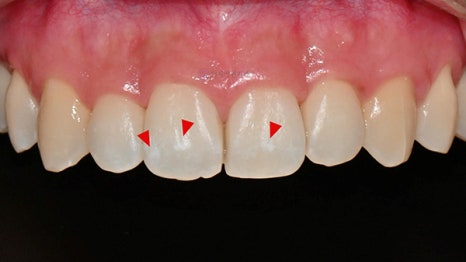

아이콘 치료 직후 사진입니다. 아이콘 치료는 치아를 깎지 않기 때문에 마취 없이 간단하게 2030분 이내 치료가 가능하다는 장점이 있습니다. 아이콘 치료시 치아 전체를 건조시킨 상태로 유지를 해야 하기 때문에 치아가 일시적으로 chalky white하게 보이지만, 실제로 침이 있는 자연스러운 구강 내 상태로 보면 사진보다 훨씬 더 심미적으로 자연스럽게 보이며, 치료 12주 정도 지나면 훨씬 더 자연스러워보입니다. 치료 직후 처음으로 거울로 본인의 치아를 본 환자분의 첫마디도 "와우!" 였습니다 :)